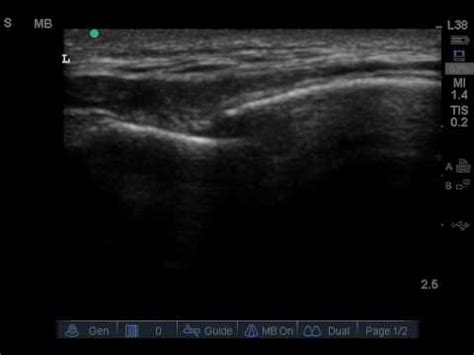

A fracture is when the continuity of a bone is broken. Pupillary reflex visual field testing (i.e., the confrontation visual field examination) abnormality. Ankle injuries are among the most common of the bone and joint injuries.

They most often occur as a result of a fall. The illustration below shows a fracture through the patella. A hip fracture is a break that occurs in the upper part of the femur (thigh bone). Lift your fractured leg about 8 inches off the floor. A fracture is when the continuity of a bone is broken. Definition of step off in the idioms dictionary. Table 1.a verage c ontactpressures in m pa (sd ). There are many different types of fracture from greenstick, hairline, and compression to oblique, impacted, and longitudinal. Step off deformity and sagging shoulder are findings of: Step off that table before you fall and crack. The fracture of a solid usually occurs due to the development of certain displacement discontinuity. 1:22:03 nicole michael recommended for you. Ankle injuries are among the most common of the bone and joint injuries. The second step is to solve the displacements and strains that occur due to pressuring a fracture with a given net pressure. Literally, to take steps down from and off of something. Intact m eniscectom y intact m eniscectom y. Symptoms may include pain around the hip, particularly with movement, and shortening of the leg.